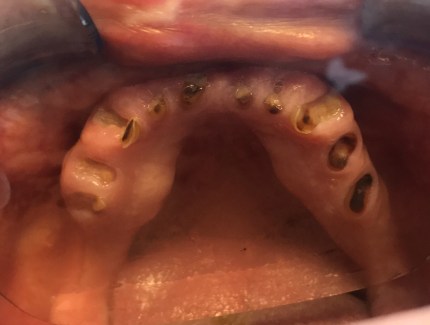

Extractions with Alveoloplasty and Lingual Tori Removal

Upper Left and Upper Right Alveoloplasty